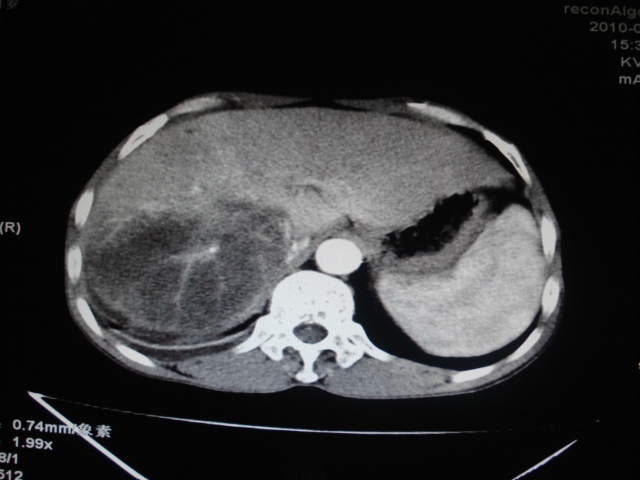

男性,62岁。肝右叶占位,平扫及增强如下,延迟期为15分钟扫描。

延迟期怎么进去了   血管瘤?